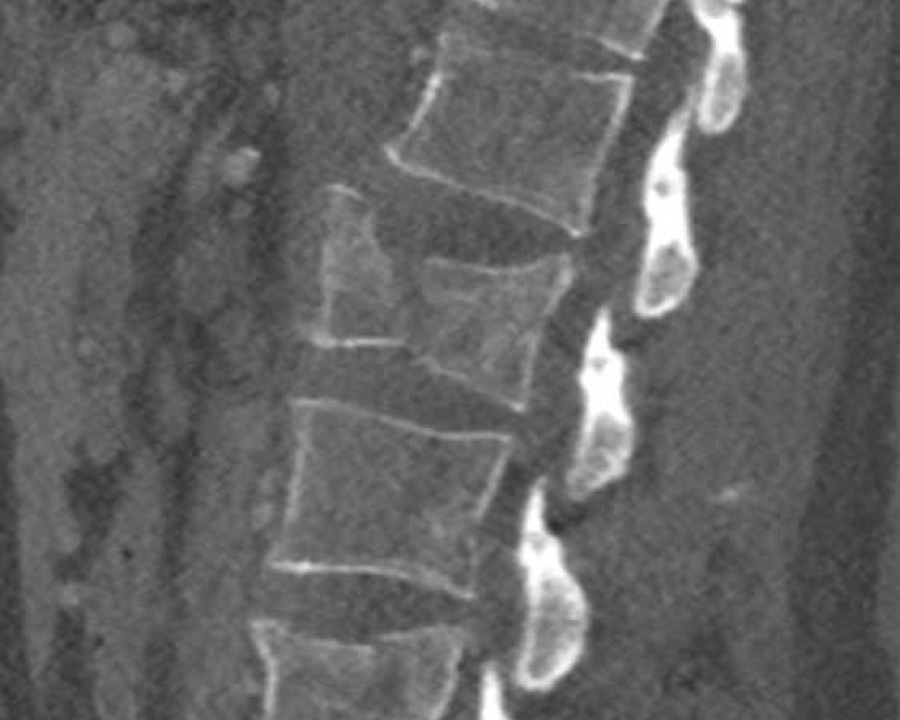

A3 Incomplete Burst fractures

Fracture with any involvement of the posterior wall; only a single endplate fractured.

A vertical fracture of the lamina is usually present and does not constitute a tension band failure.

Findings:

- No C or B injury

- Fractures vertebral body with involvement of upper endplate (1 point) and posterior wall (2 points)

Conclusion

Injury type A3